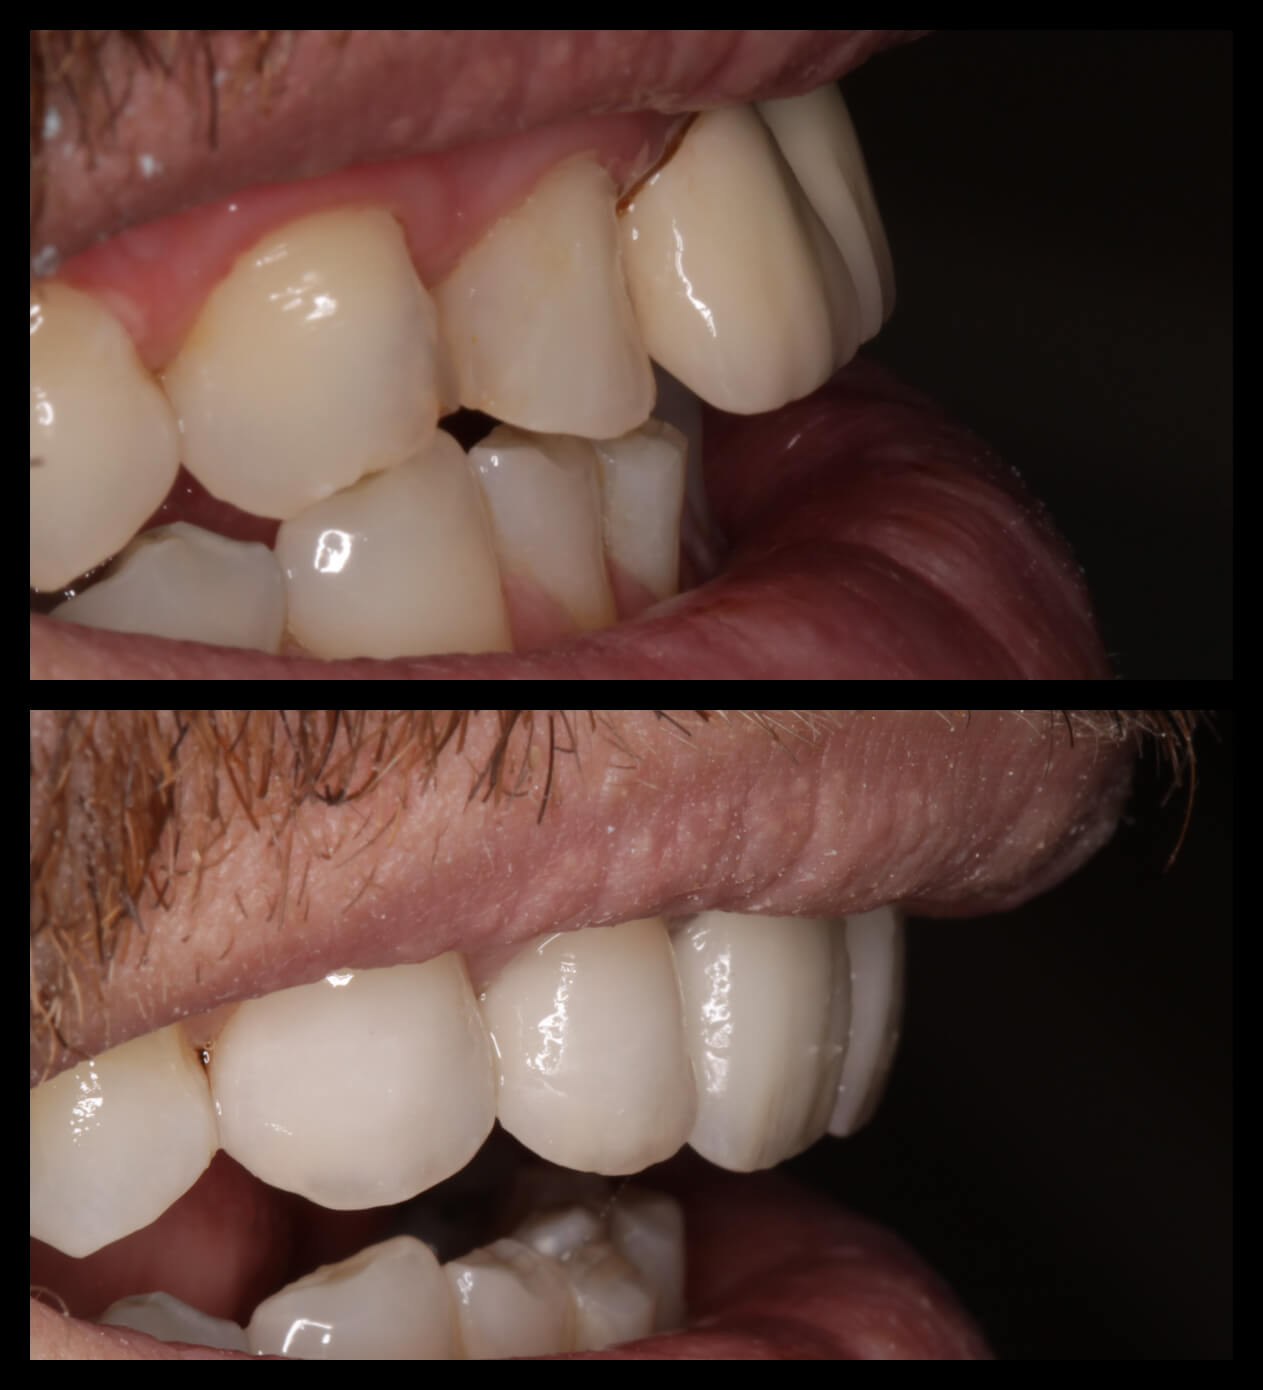

ΠΡΟΣΘΕΤΙΚΕΣ ΑΠΟΚΑΤΑΣΤΑΣΕΙΣ ΜΕ ΣΥΝΔΥΑΣΜΟ ΛΕΥΚΑΝΣΗΣ, ΣΥΝΘΕΤΩΝ ΡΗΤΙΝΩΝ ΚΑΙ ΟΛΟΚΕΡΑΜΙΚΩΝ ΟΨΕΩΝ ΚΑΙ ΣΤΕΦΑΝΩΝ

ΠΕΡΙΣΤΑΤΙΚΑ ΜΕ ΤΟΠΟΘΕΤΗΣΗ ΕΝΔΟΟΣΤΙΚΩΝ ΕΜΦΥΤΕΥΜΑΤΩΝ. ΌΠΟΥ ΧΡΕΙΑΣΤΗΚΕ ΠΡΑΓΜΑΤΟΠΟΙΗΘΗΚΕ ΑΝΑΠΛΑΣΗ ΟΣΤΟΥ ΚΑΙ ΟΥΛΙΚΩΝ ΕΛΕΙΜΜΑΤΩΝ ΜΕ ΧΡΗΣΗ ΜΟΣΧΕΥΜΑΤΩΝ ΚΑΙ PRF